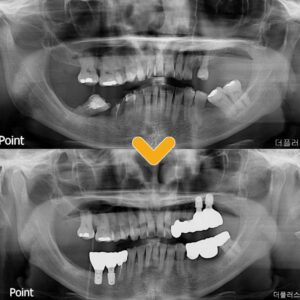

12. 수암동치과 치아를 보존하기 위한 마지막방법으로

수암동치과 치아를 보존하기 위한 마지막방법으로 안녕하세요. 모든 진료에 진심을 다하는 곳, 더플러스치과 입니다. ​ 모든 치료가 그렇다시피 치과 치료에도 적절한 시기가 있는데요.   이를 지나치게 되면 자연 치아를 보존하기 힘들어질 수 있습니다.   아무리 의료기술이 발달하고 있다고 해도 자연치아를 완벽히 대체할 순 없기에 시기를 놓치지 않도록 정기적으로 검진을 받는 것이 더보기…